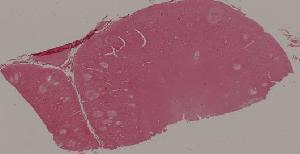

94.乙型脑炎